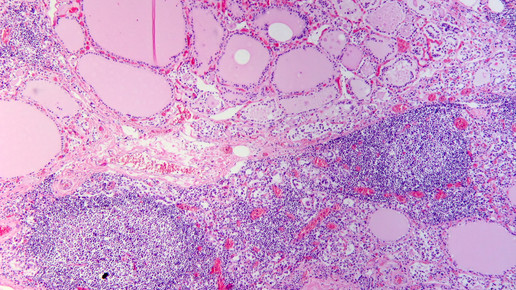

Ist das Organ dauerhaft entzündet, greift das körpereigene Abwehrsystem fälschlicherweise das Gewebe der Schilddrüse an. Mit Thyroxin-Tabletten lässt sich die Krankheit behandeln. Dabei ersetzten die Medikamente das körpereigene Hormon und der Stoffwechsel wird normalisiert.